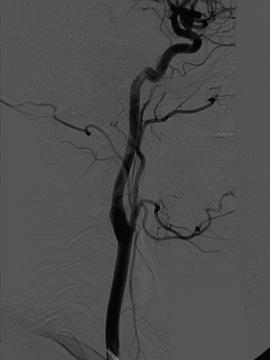

Functions of the cerebrum include: We are pushing the boundaries of what's possible in brain, spine, and pain management, all in service to you. Nerves extend from your brain and spinal cord, sending important messages throughout your body. Commonwealth spine & pain specialists, board certified spine & pain specialists in richmond, va are experts in diagnosing and treating chronic pain.